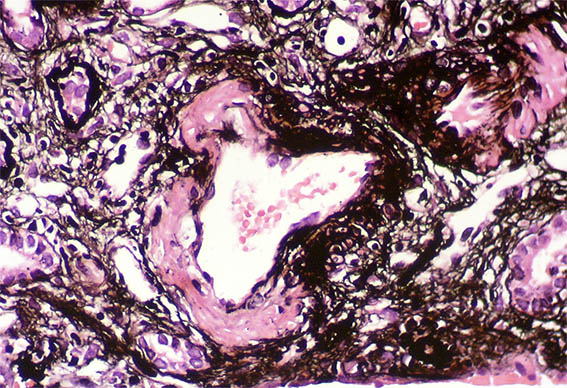

Figura 11. Plata-metenamina, X400.

Inmunofluorescencia para IgA, IgG, IgM, C3, C1q, kappa, lambda y fibrinógeno: negativas.